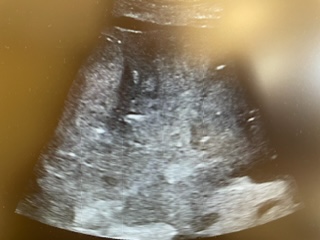

Descripción de los hallazgos ecográficos y las imágenes más relevantes para la resolución del caso

Realizamos POCUS en consulta y objetivamos líquido libre abdominal, así como hígado heterogéneo con distorsión grosera del parénquima, donde se objetivan dos lesiones hipoecogénicas de menos de 2 cm de longitud.